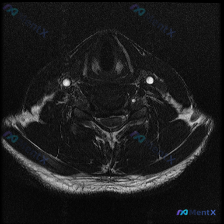

今天碰到一个有意思的情况:临床提示椎间盘病变,只给了一张颈部MRI T2序列轴位图像,咱们一起来理理思路。 病例基本信息 这是一张颈椎下段(推测C5-C6或C6-C7椎间盘水平)的T2轴位MRI,我们先读片: 1. 脊髓:信号均匀,没有明显异常高信号水肿或低信号出血,形态正常 2. 脑脊液:T2高信...

刚整理了一份很有临床意义的读片病例,怀疑椎间盘病变但单幅影像没有明显异常,把我的分析思路分享给大家。 病例影像基本信息 这是一份颈部MRI轴位T2加权像,扫描层面大致位于颈椎下段C5-C6或C6-C7椎间盘层面,图像质量清晰,没有明显伪影。 影像具体观察结果 1. 椎体:椎体后缘轮廓规整,骨髓信号均...

看到一个有意思的读片病例,整理了完整的分析思路分享给大家。 病例基本信息 核心问题:临床怀疑颈椎间盘病变,提供单张颈部MRI T2加权轴位影像,请判断病变情况。 影像学观察结果 这张图像是颈椎中下段水平的标准T2加权轴位影像,对比度良好无明显运动伪影,影像观察结果如下: 1. 椎间盘与骨性结构: 椎...